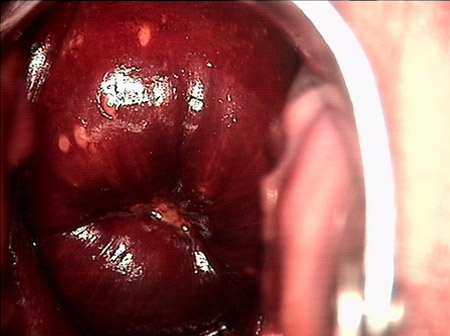

婦科leep手術(shù) 宮頸息肉

宮頸息肉